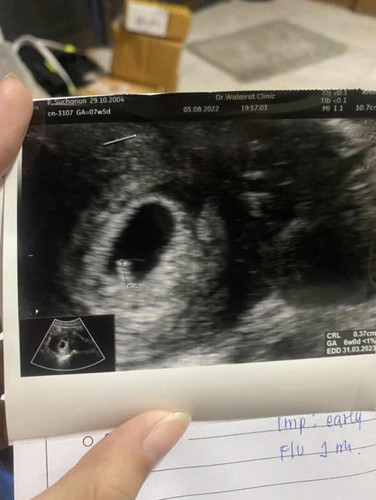

แบบนี้ยังมีหวังอยู่ไหมคะ ซาวครั้งแรกตอน4wไม่เจอตัวน้อง 6wเห็นตัวแต่ไม่เห็นหัวใจเต้นคุณหมอมั่นใจว่าเป็นตัวอ่อนเสียชีวิตแต่ยังให้โอกาสอีก1อาทิตย์ คุณแม่ไม่มีอาการปวดท้องหรือเลือดออกใดๆเลย จะมีหวังไหมคะ#ท้องแรกคะ #ขอคำคิดเห็นหน่อยคะ #แท้ง

บ้านนี้ 6wยังไม่เจอแม้แต่ถุงตั้งครรภ์เลยค่ะ หมอบอกไม่แน่ใจนะว่าจะท้องนอกมดลูกมั้ยอีกสัก4wค่อยมาซาวด์ใหม่ แม่เสียใจมากค่ะ ตัดสินใจลองเปลี่ยนหมอเปลี่ยนคลินิก ไปตอน8w เจอทั้งตัวอ่อนและหัวใจค่ะ ผลซาวด์ออกมาตัวอ่อนยาวเกือบ 2 เซนติเมตร ณ ตอนนี้ 22wแล้วค่ะ คุณแม่ทำใจให้สบายนะคะ ดูจากใบซาวด์น้องยังเล็กมาก ไม่ถึงครึ่งเซนเลยค่ะ หรืออาจลองซาวด์ที่คลินิกอื่นดูด้วยก็ได้ค่ะ

อ่านเพิ่มเติมเอาจริงๆ เเต่6สัปดาห์ ส่วนใหญ่ไม่ค่อยเจอหรอกค่ะ บางทีไข่ตกช้า ของเรา6วัปดา ไม่เจอไข่เเดงด้วยซ้ำ หมอนักมาหลังจากนั่น อีก 2สัปดาห์ ถึงเจอทั้งคนทั้งไข่ทั้งหัวใจ เเต่ก็เล็กมาก หมอเลยขออีก 2สัปดาห์ ทีนี้เเหล่ะ มาเป็นลูกอ๊อดพร้อมเเขนขาน้อยๆมาเชียว

เราตรวจเจอถุงตอน 5 weeks คุณหมอบอกตั้งครรภ์ แต่นัดให้มาเจออีก 7 weeksตอนนั้งก็ยังไม่เจอตัวน้องค่ะ หมอบอกงั้นมาใหม่นะครับคุณแม่ ของเราเจอหัวใจตอน 9weeks ค่ะ ใจเย็นๆนะคะคุณแม่ ทานยาบำรุงตามหมอสั่งเดี๋ยวก็เจอแล้วค่ะ

เคยเป็นเหมือนกันค่ะ ท้องที่2 รู้ว่าท้องตอนอายุครรภ์ได้6 wพอไปหาหมอเจอแต่ถุงการตั้งครรภ์แต่ไม่มีเสียงหัวใจ หมอนัดมาใหม่ตอนครบ 10 wค่ะ คราวนี้ได้ยินเสียงหัวใจชัดเจนค่ะ อย่าพึ่งเครียดนะคะ